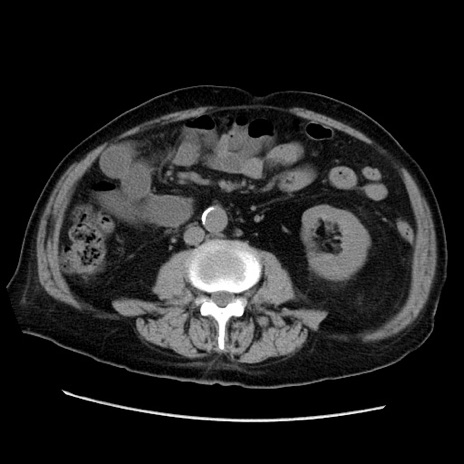

冠状断像

症例21(横断像)

【症例】70歳代男性

【主訴】腹痛

【現病歴】肝硬変・肝細胞癌にてかかりつけの方。約9時間前に食後より腹痛出現。症状が徐々に増悪し、嘔吐出現したため来院。

【既往歴】肝硬変、肝細胞癌(RFA、TACE後)

【身体所見】意識清明、表情苦悶様、BT 36℃、BP 129/78mmHg、P 88bpm、SpO2 97%(RA)、右上腹部から心窩部にかけて圧痛あり、反跳痛なし、筋性防御あり。

【データ】WBC 5800、CRP 0.16